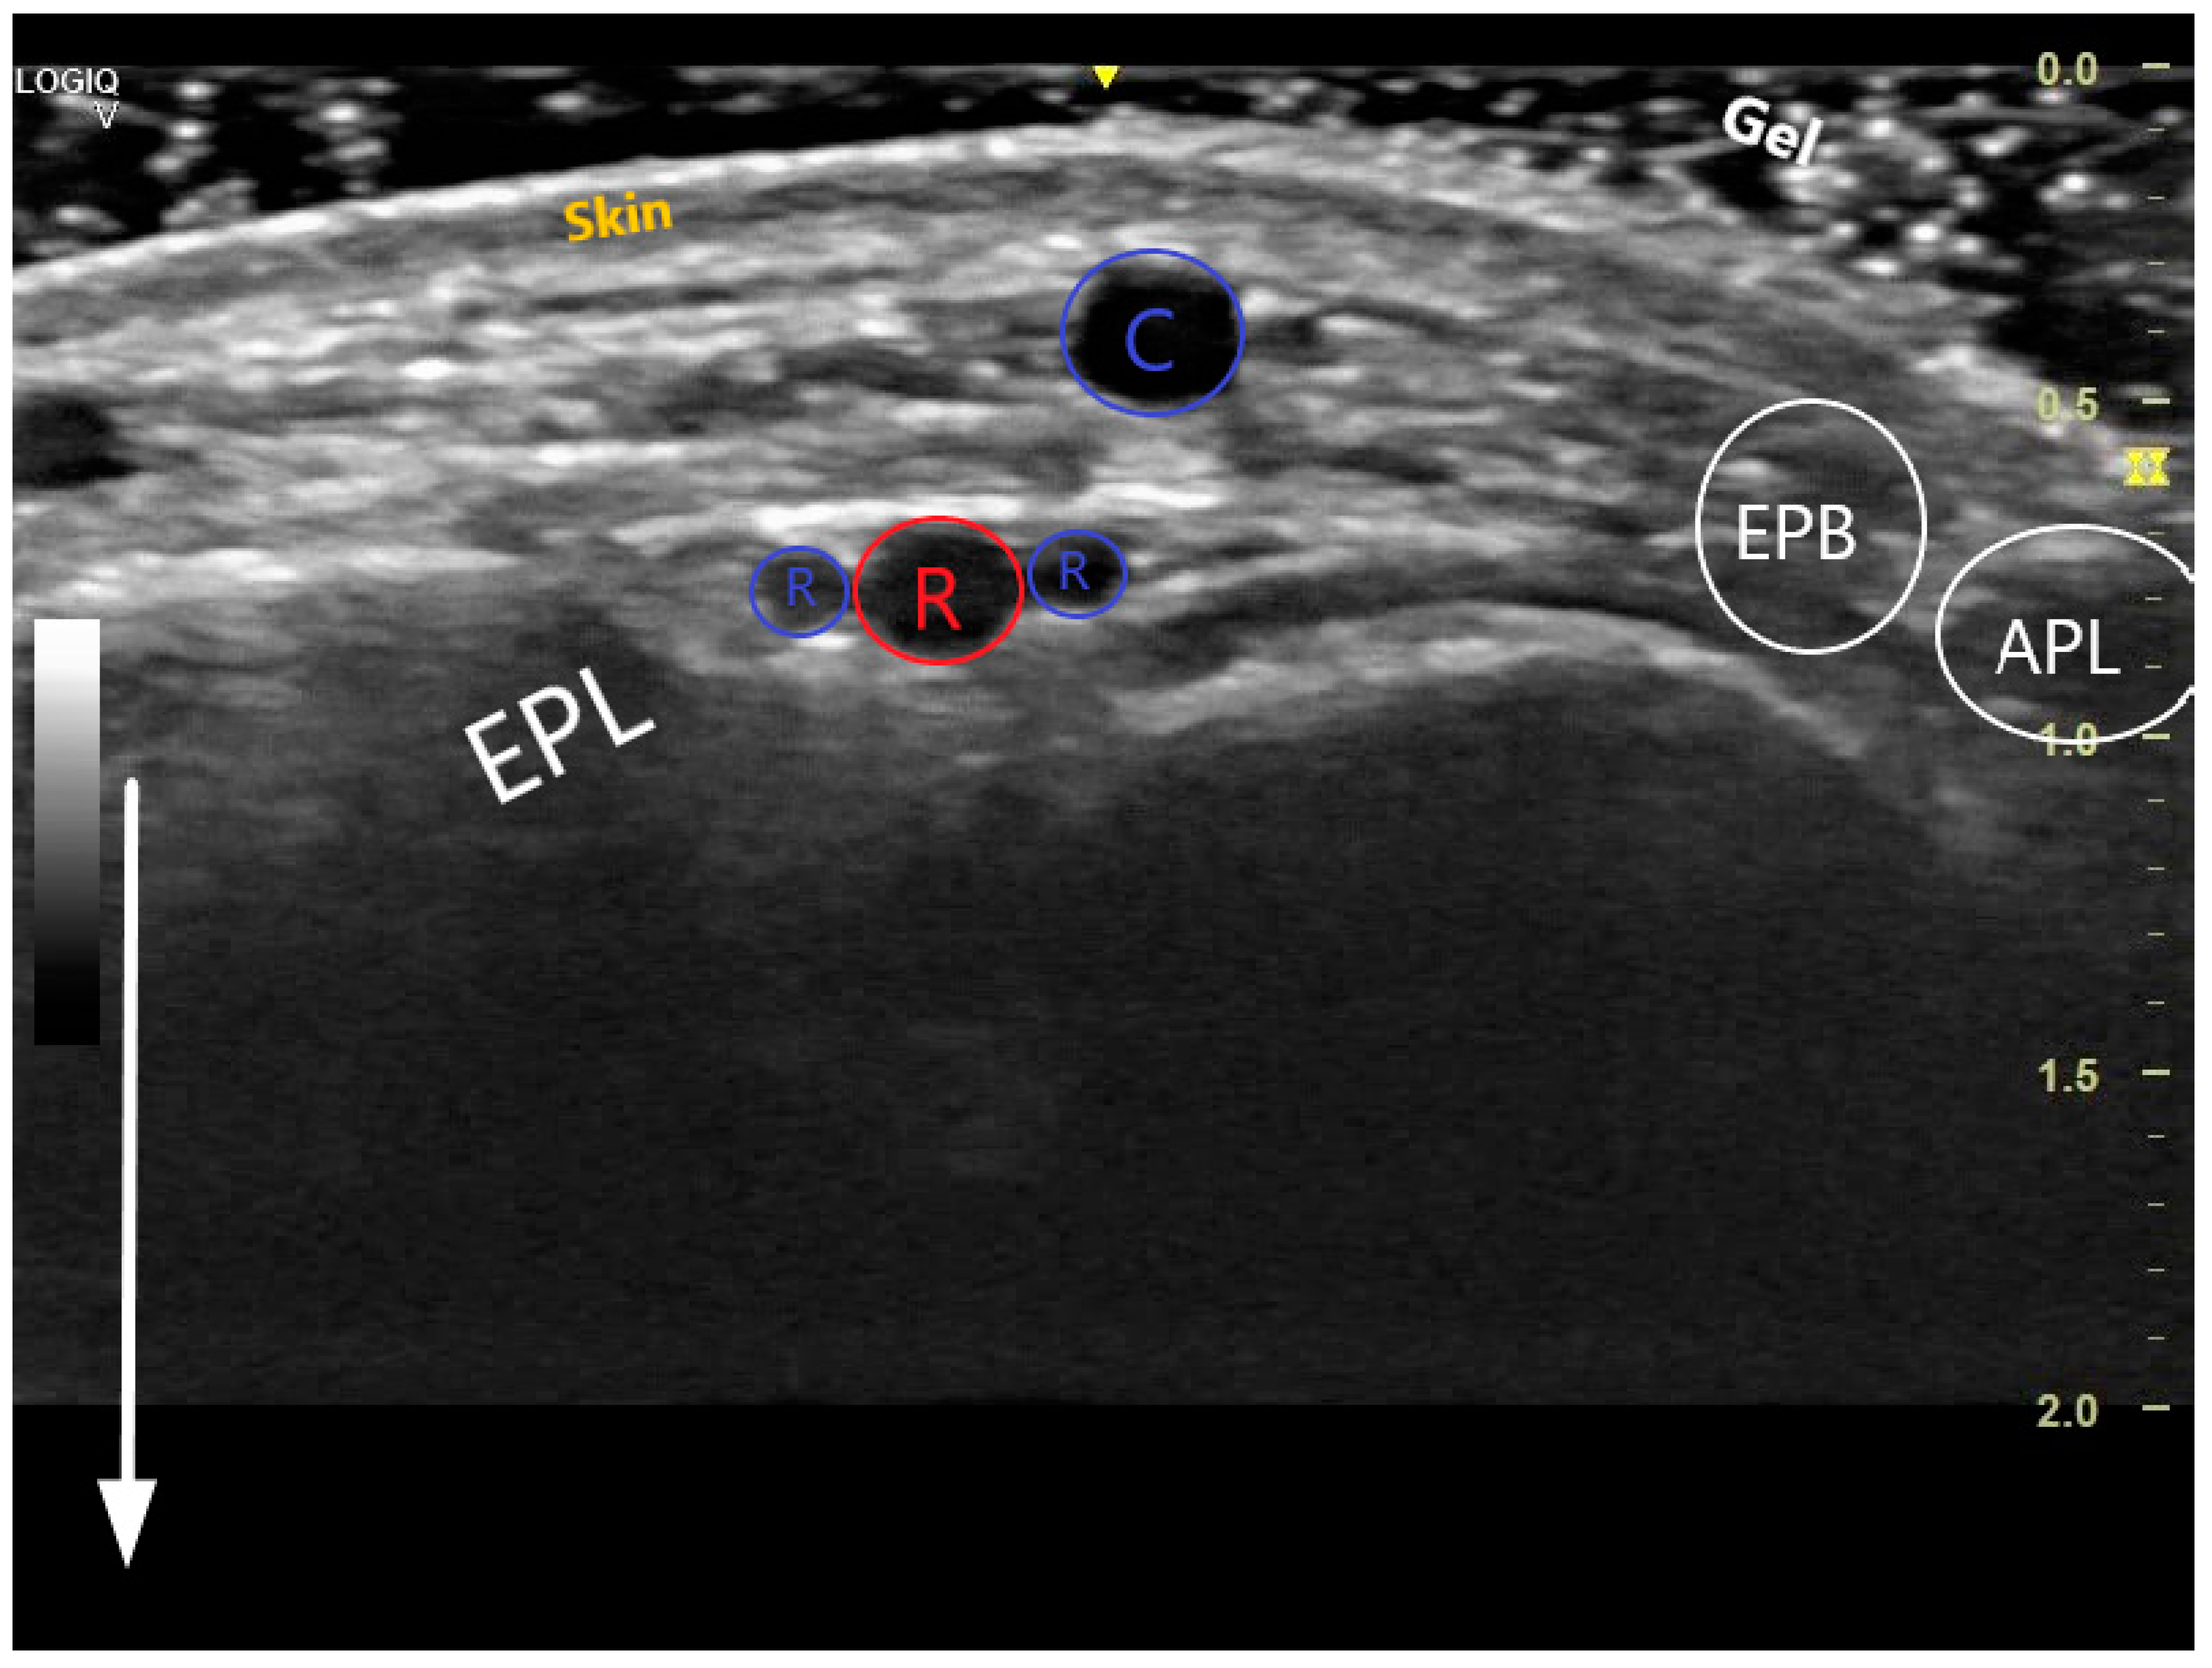

Figure 2.

Transversal US image at the anatomical snuffbox. The depth has been adjusted so that the structures near the transducer form the majority of the image. The white arrow demonstrates the near and the far during scanning. The 3 layers of the skin are visible, superficially is the cephalic vein (C), deeper the radial artery (red R) accompanied by 2 radial veins (blue Rs). The snuffbox is surrounded by the extensor pollicis longus (EPL), extensor pollicis brevis (EPB), abductor pollicis longus (APL), and scaphoid (S).